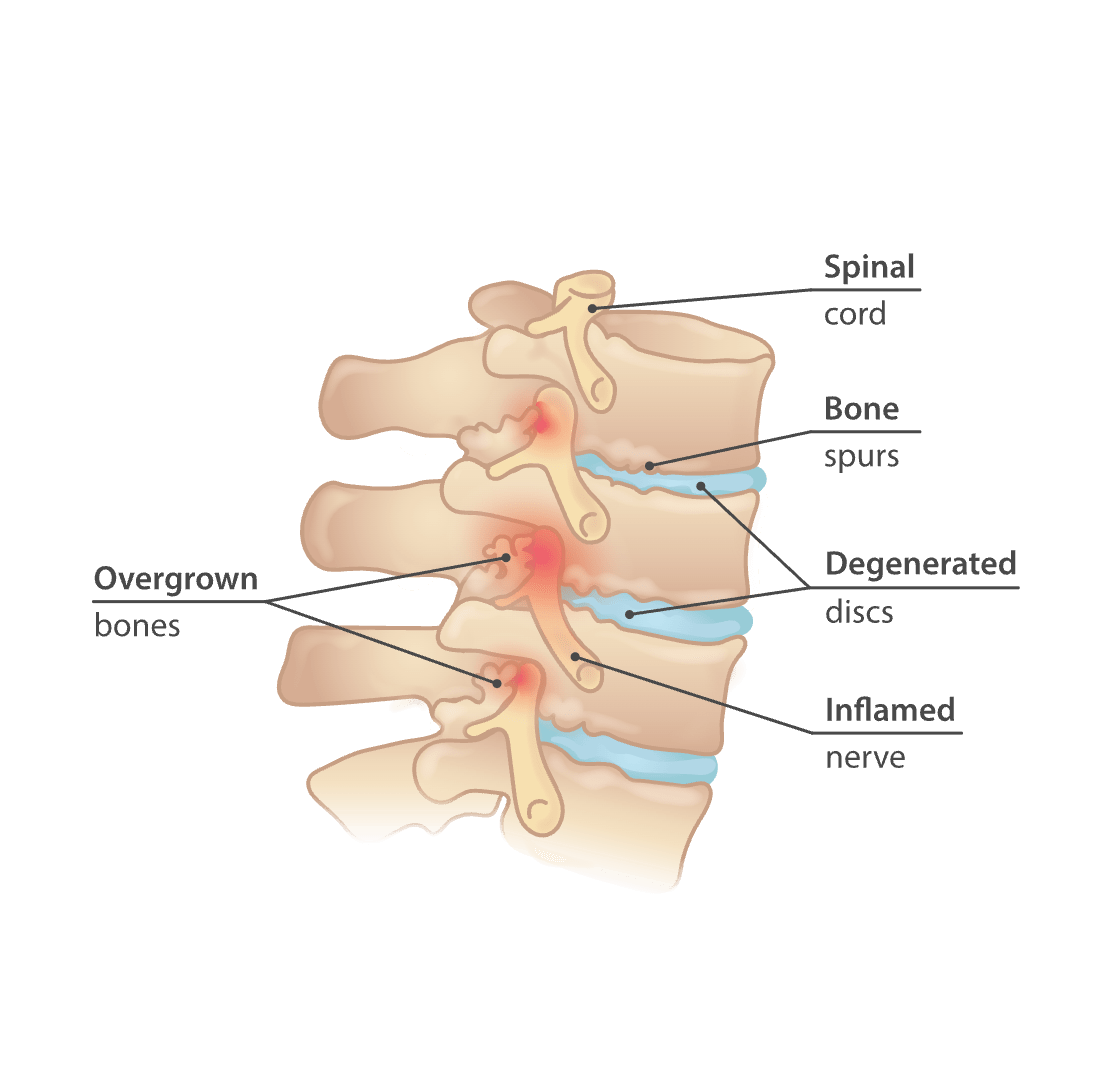

Bone Spur – Osteophytes, Causes, Signs, Symptoms & Treatment

Bone Spur – Osteophytes, Causes, Signs, Symptoms & Treatment

Bone spurs in neck (cervical osteophytes): Causes, symptoms, diagnosis …

Arthritis (Spine) And Bone Spurs

Bone Spur – Osteophytes, Causes, Signs, Symptoms & Treatment